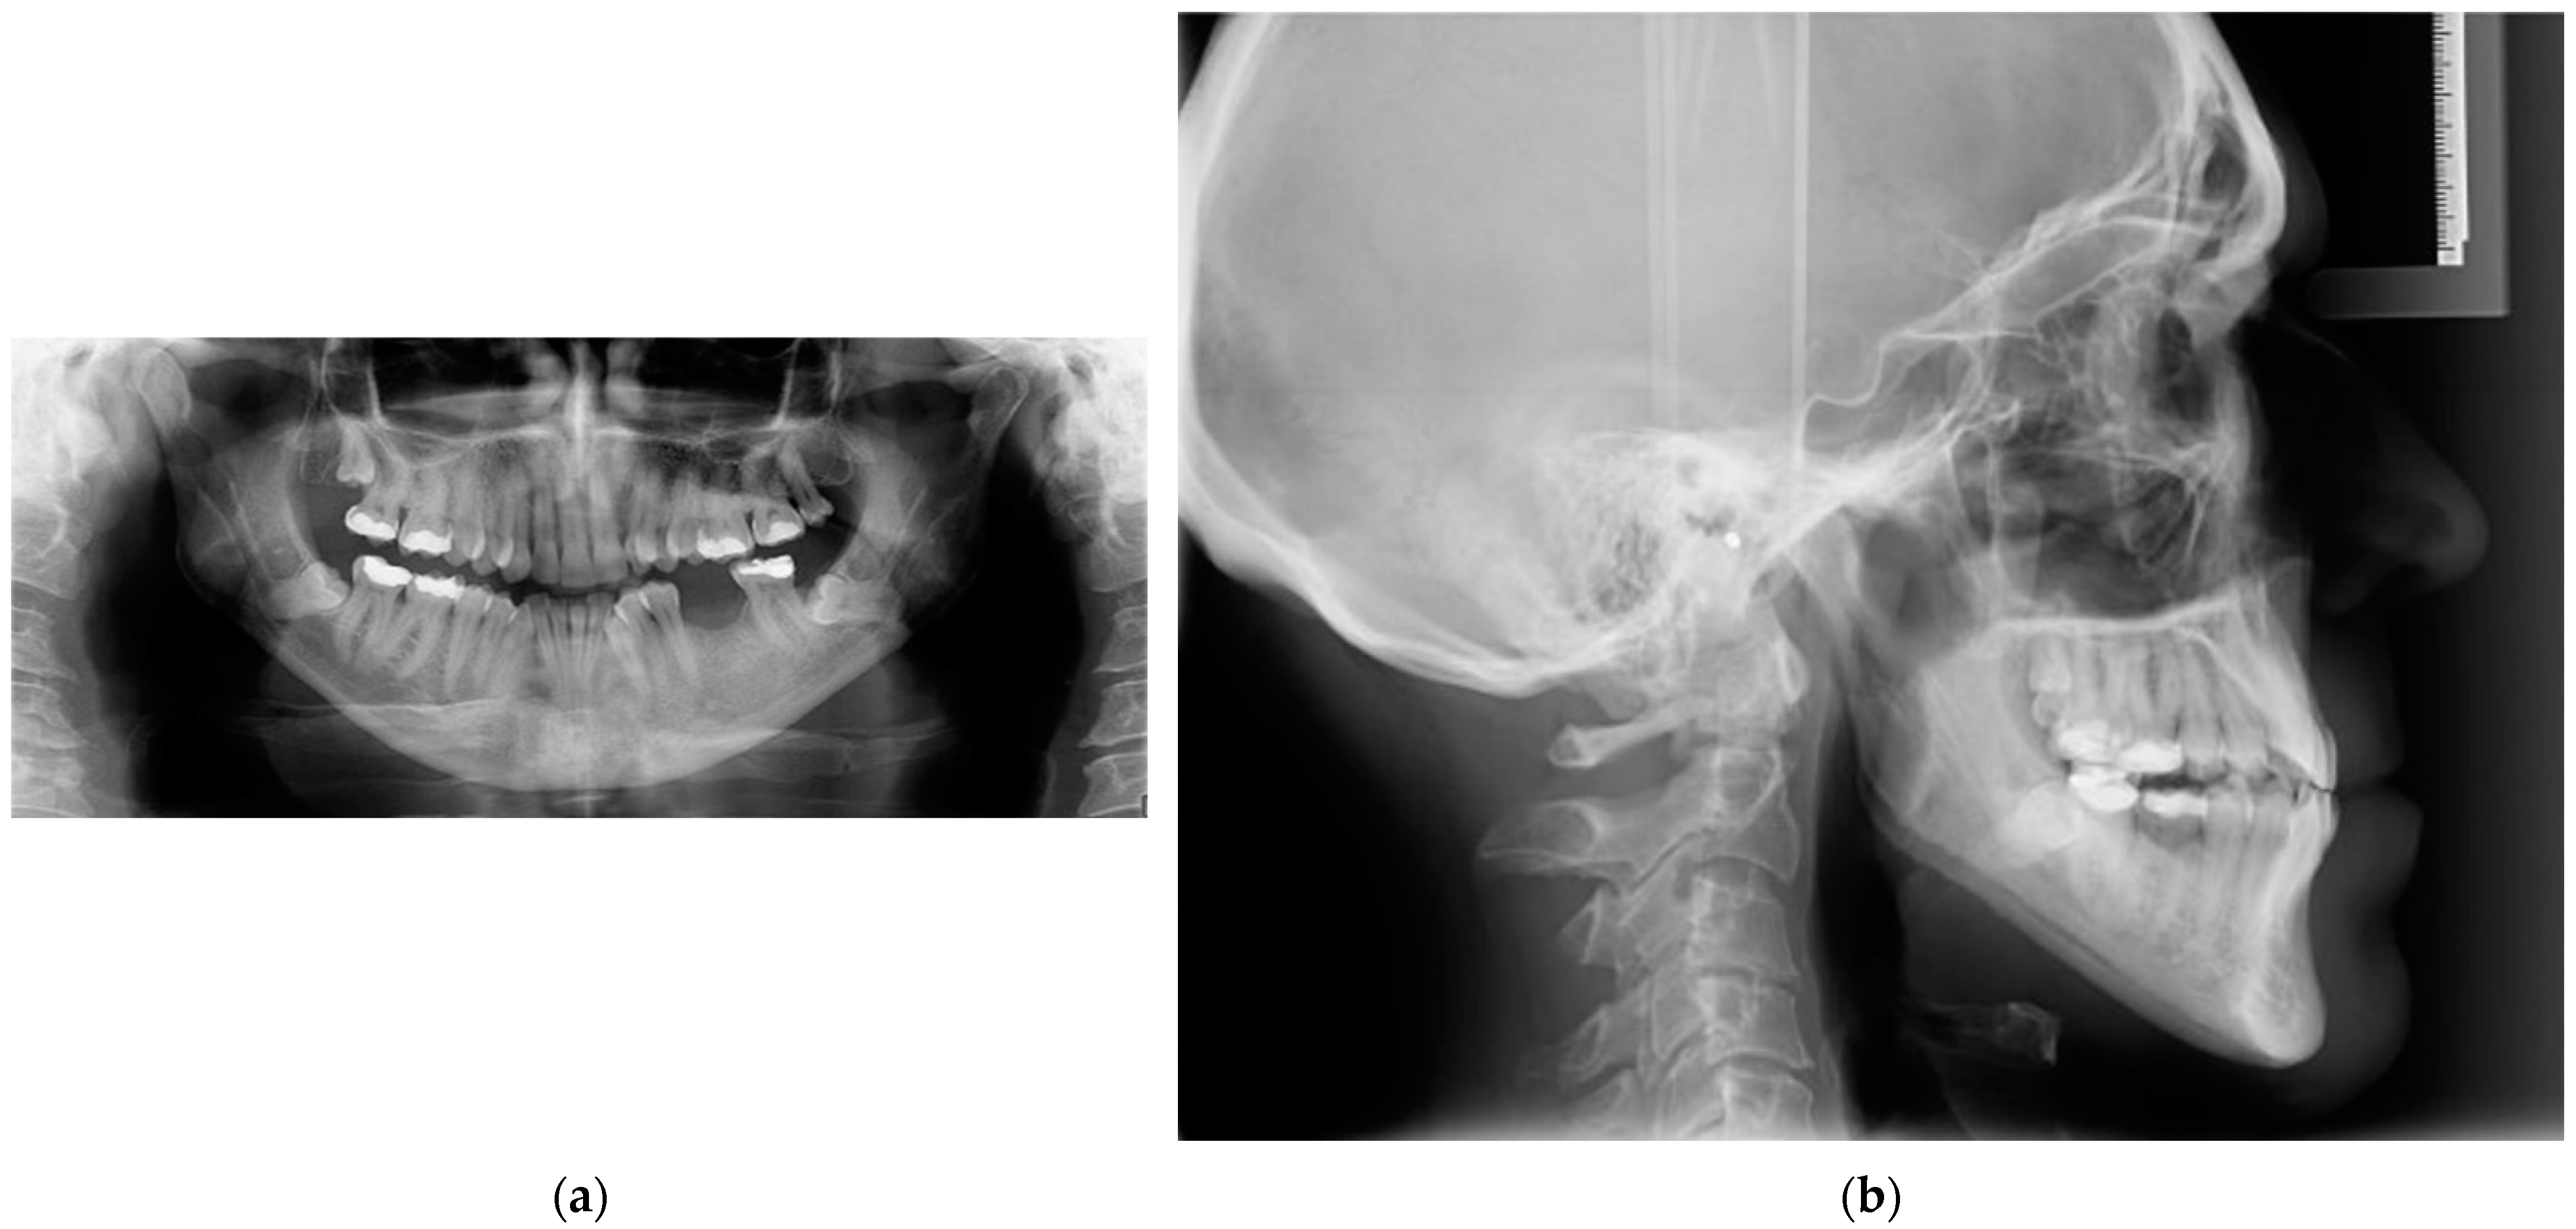

2. Case Report